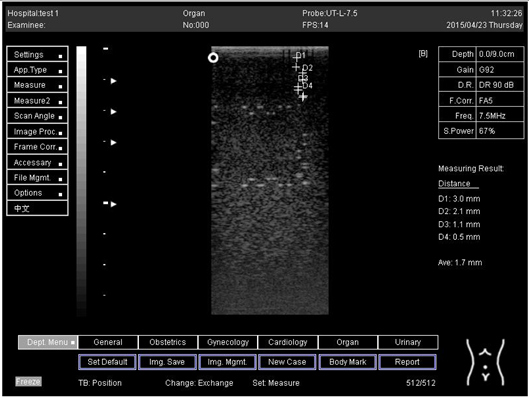

Table 6. The distance for axial and lateral resolution in mm for depth of 5.0, 6.0, 7.0 and 9.0 cm; depth for flat probe on phantom 2.

Depth (cm)DiagramDistance (mm)

5.0Axial resolution

Biomimetics 07 00130 i011

D1 = 3.0

D2 = 2.0

D3 = 1.0

D4 = 0.5

5.0 Lateral resolution

Biomimetics 07 00130 i012